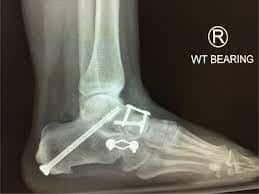

To improve the biomechanics of the tendon transfer the heel bone is moved towards the inside of the foot (calcaneal osteotomy) and held with screw fixation. In addition, a plug may is inserted into the outer portion of the foot to assist in supporting the arch. If required the plug and/or screws can be removed in a second operation when they have served their purpose and the tendon is healed. Additional procedures such as synthetic tissue augments, lengthening of the achilles tendon and other bony surgery may be required and will be discussed if thought necessary.